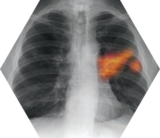

Le bilan initial comprend un examen clinique, une radiographie thoracique dont la normalité n’élimine pas un cancer bronchique, des explorations biologiques et fonctionnelles respiratoires et cardiovasculaires. Le bilan est complété par un scanner thoracique avec injection de produit de contraste en l’absence de contre-indication.

Le bilan d’extension (scanner thoracique et abdominopelvien, scanner ou IRM cérébrale, tomographie à émission de positons -TEP ou Pet-Scan- ou, à défaut, scintigraphie osseuse) évalue l’envahissement locorégional ou à distance (atteinte ganglionnaire ; présence de métastases cérébrales, surrénaliennes, hépatiques et/ou osseuses).